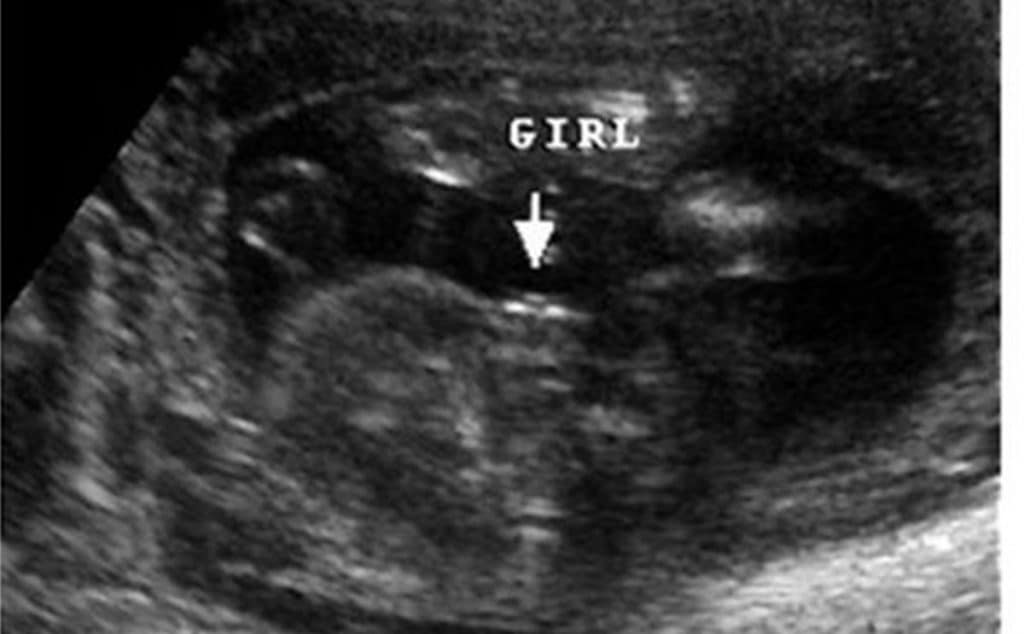

• فحص السونار منذ خمسينيات القرن الماضي بدأ استخدام أجهزة الأمواج فوق الصوتية (Ultrasound) في مجال الطب وخصوصًا في مجال الحمل والولادة، وأصبح بالإمكان معرفة نوع الجنين منذ الأسبوع الرابع عشر من الحمل.

• حيث يتم ذلك من خلال عملية تصوير بسيطة بالأمواج فوق الصوتية يقوم بإجرائها طبيب النساء، وتتيح معرفة جنس الجنين من خلال رؤية العضو التناسلي لدى الجنين، ومعرفة جنسه مبكّرًا. الأمر الإيجابي هو أن هذا الفحص يتيح للزوجين إمكانية الاستعداد للمستقبل، سواء من حيث اختيار اسم المولود أو حتى على مستوى شراء وتجهيز الاحتياجات واللوازم.

• لابد أن نعرف أن تحديد نوع الجنين يكون بالكشف عن الأعضاء التناسلية، والتي تبدأ بالتطور في مرحلة الأسبوع الثالث من الحمل، ولكن على الرغم من ذلك إلا أن أجنة الذكور والإناث يبدون متشابهين بشكل تام عند التصوير بالموجات فوق الصوتية في الثلث الأول من الحمل وحتى الأسبوع الـ 14 من الحمل.

• وبحلول الأسبوع الـ 18 يكون باستطاعة الطبيب أن يقوم بالكشف عن نوع الجنين أو جنسه، وذلك إن لم يكن الجنين نائماً بوضعية تجعل الأعضاء التناسلية غير واضحة.

• فبحلول الأسبوع الـ 18 من الحمل يمكن أن نعرف نوع الجنين باستخدام جهاز الموجات فوق الصوتية بالكشف عن الأعضاء التناسلية للجنين. ويعد تحديد الأنثى أسهل من تحديد الذكر، حيث أن رؤية شفرتي المهبل تكون علامة أكثر قطعية على أن الجنين أنثى، ويختلف تطور الأجنة عن بعضها، ووضح الأعضاء التناسلية يعتمد بشكل أساسي على سمك جدار بطن الأم وكذلك وضعية الجنين.